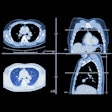

ECR: AI enhances detection of pulmonary nodules